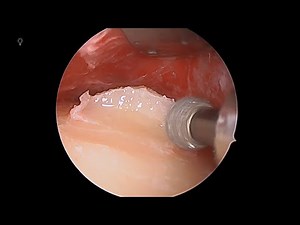

Endoscopic removal of forehead osteoma

Dr. Joseph Niamtu shares a case of endoscopic removal of forehead o